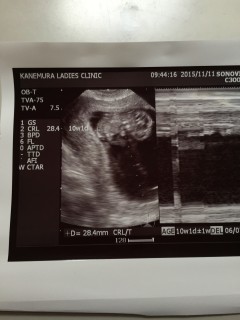

妊娠10週0日です。元気よく手をブンブン振ってました(^_^)/ 胎児は2.8㎝に成長してました。 次は4週間後の14週目の予定です。

2週間ぶりに会えました~先生に順調だと言われて安心しています。大きさは2.9センチ。手をぱたぱた振っていました。次は12週目健診です。2週間、長いなぁ。